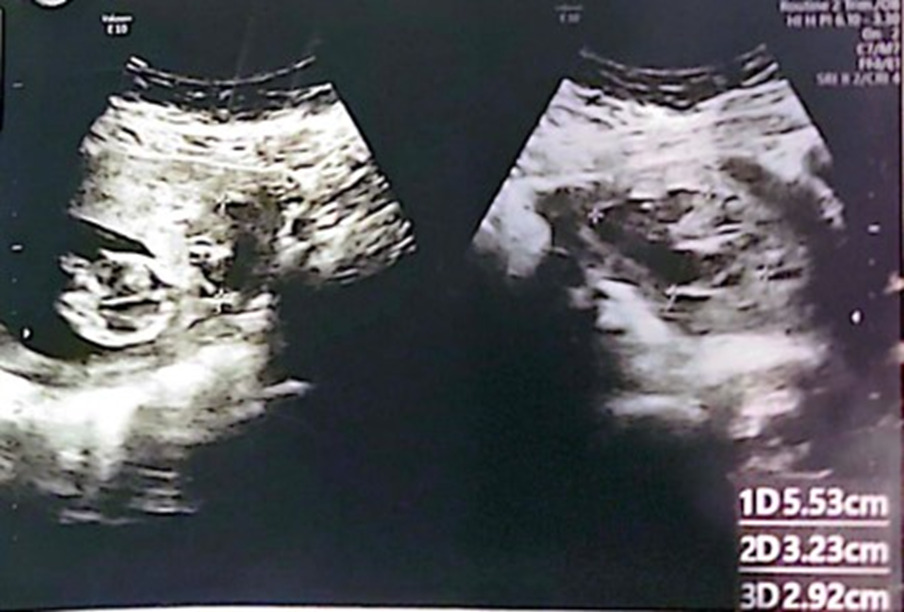

30-year-old female G3P1+1+0+2 14+2 weeks of gestation previous one cesarean section due to failure to progress and a known case of bicornuate uterus presented to the emergency department with lower abdominal pain and bleeding per vagina. She was admitted for observation as a case of threatened miscarriage. Ultrasound done showing bicornuate uterus with single living fetus matching date in the right cornua and a sub chorionic hematoma (SCH) measuring 55x32x29 mm in the left cornua (as shown in figure 1).

Figure 1: Bicornuate uterus with fetus in right cornua and SCH in left cornua